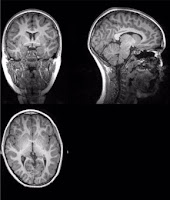

* Des études d’imagerie réalisées chez des personnes avant et après l’infection par le SARS-CoV-2 révèlent une réduction du volume cérébral et une altération de la structure du cerveau après l’infection ;

Les scientifiques ont étudié les changements survenus dans le cerveau de 785 participants à la UK Biobank, une base de données biomédicales à grande échelle et une ressource pour la recherche. Les participants étaient âgés de 51 à 81 ans et ont subi deux scanners cérébraux, à 38 mois d'intervalle en moyenne, ainsi que des tests cognitifs.

L'étude a mis en évidence un certain nombre d'effets chez les participants infectés par le SRAS-CoV-2, en moyenne 4,5 mois après l'infection, notamment une réduction plus importante de l'épaisseur de la matière grise dans les régions du cerveau associées à l'olfaction.

Les participants ont montré des signes de lésions tissulaires accrues dans les régions liées au cortex olfactif primaire, une zone liée à l'odorat, et une réduction de la taille du cerveau entier.

En moyenne, les participants ont également montré une plus grande déficience cognitive entre leurs deux scanners, associée à l'atrophie d'une partie spécifique du cervelet, une structure cérébrale liée à la cognition.

Les chercheurs ont constaté que 96% des participants présentaient une perte de volume de matière grise et des lésions tissulaires plus importantes. Ils ont également constaté un déclin plus important de leurs capacités mentales à effectuer des tâches complexes, et ce déclin mental était en partie lié à ces anomalies cérébrales. Tous ces effets négatifs étaient plus marqués à un âge avancé.